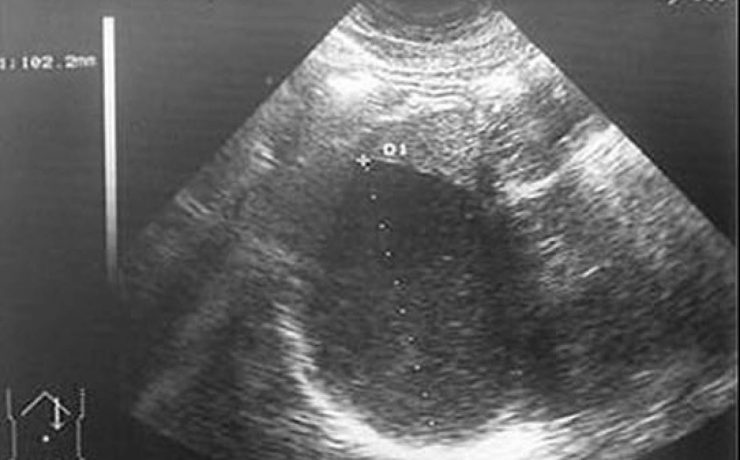

Patología fetal segundo trimestre

El RCIU constituye una de las mayores complicaciones del embarazo en. En incidencia de 3 a 10% en países desarrollados y 30% en países en vías de desarrollo. Recién nacidos con RCIU expuestos a riesgos de morbimortalidad neonatal por asfixia perinatal, encefalocele, hipoxia –isquémica, circulación fetal persistente, enterocolitis necrosante etc…